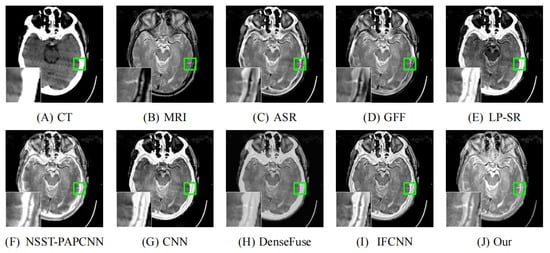

As illustrated in Figure 8, Figure 9, Figure 10, Figure 11 and Figure 12, we select fusion results of five pairs of images as the visual comparison. Among these figures, source images (CT and MRI) are shown in (A) and (B). (C) to (J) are fusion results obtained by various fusion methods. Every image has an enlarged subimage in the lower-left corner that is useful for visual assessment.

Although it’s hard to assess the visual effects of these results accurately, significant differences are observed. Figure 8, Figure 9, Figure 10, Figure 11 and Figure 12 show CT images that are high-resolution in dense structures such as bones and implants but low-resolution in soft tissues. MRI images can offer high-resolution edge and anatomical information for soft tissues. However, the other seven methods are affected to varying degrees by the low-resolution soft tissues information of the CT images. It may cause the fused image with fewer details and blurred contours. ASR is a TD-based method that calculates weight maps by some pre-trained dictionaries. The results of ASR have a low contrast ratio and halo effect. As illustrated in Figure 8, the enlarged subimage of ASR has a low contrast ratio and the bone of fused image has a black halo. GFF is a TD-based method. This method decomposes the source images into base layer and detail layer. Then, multiple filters, such as average filter and guided filter, are utilized to merge the features. Thus the contrast is poor in the fused images obtained by GFF. Figure 9 shows that a part of bone in the enlarge subimage is missing. LP-SR and NSST-PAPCNN are mixed fusion methods, which employ MST to decompose the source image and then use different strategies to fuse the high-frequency features and the base features, respectively. LP-SR employs Laplacian pyramid to decompose the source image and then uses the “choose max” rule to fuse the high-frequency features. The multi-scale decomposition and activity level measurements are required for MST-based fused results. This may result in the loss of some details. For example, in Figure 8 and Figure 11, the fused image of LP-SR is more close to the CT image and lose the detail and structure information of MRI image. NSST-PAPCNN employs NSST to decompose the source image and then uses PAPCNN to fuse the detail textures. The soft tissue detail of fused image by NSST-PAPCNN is close to our fusion result, whereas is fuzzier in the edge detail, such as the enlarged part of Figure 11. CNN, DenseFuse and IFCNN are DL-based methods. However, CNN uses LP and GP to fuse the extracted features, which leads to the loss of details from MRI images. Similar to LP-SR, we can also observe the fused image of CNN lose the detail and structure information in the Figure 8 and Figure 11. Similar to our proposed method, DenseFuse uses an encoder-decoder architecture, but the l 1 N o r m strategy is used in the fusion block. This strategy may make the detail textures of fused images by DenseFuse be smoothed, which can be observed in all the five fused results. Different to our proposed method, IFCNN adds the fusion block to the training phase. It selects elementwise-maximum as the fusion strategy. However, the contrast is lower than our proposed method and the edge detail is not clear enough in the fused result by IFCNN. Overall, the comparison experiment demonstrates our method preserves more textual details and clearer edge information. In addition, due to the higher contrast, our fused images are friendly to human vision.

Figure 9. Fusion images of “Acute stroke speech arrest-16” by various methods. From (A) to (J): CT, MRI, ASR, GFF, LP-SR, NSST-PAPCNN, CNN, DenseFuse, IFCNN, Our proposed method.

Figure 11. Fusion images of “Fatal stroke-14” by various methods. From (A) to (J): CT, MRI, ASR, GFF, LP-SR, NSST-PAPCNN, CNN, DenseFuse, IFCNN, Our proposed method.